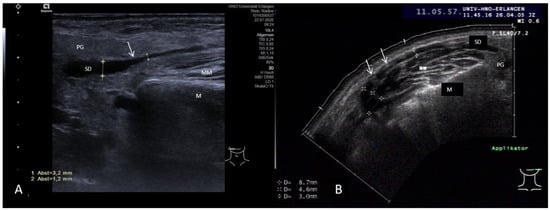

3.3.2. Obstructive Sialadenitis Caused by Sialolithiasis